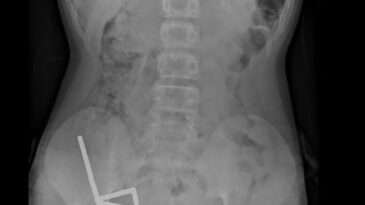

Yeni Zelanda'da 13 yaşındaki bir çocuk, internette satın aldığı yaklaşık 100 yüksek güçlü mıknatısı yuttuktan sonra ameliyata almak zorunda kaldı. Kuzey Ad...